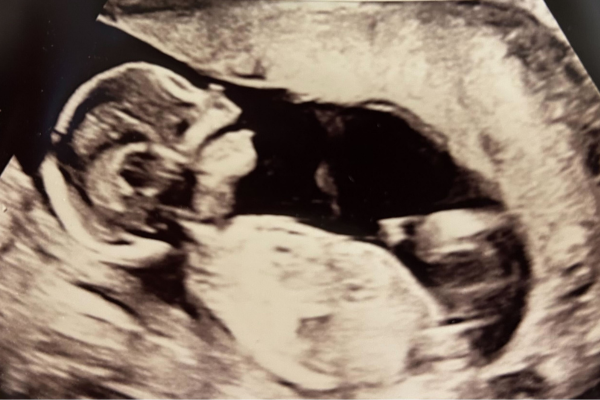

Gravid uge 16

Uge 16+0 – 16+6

Barnet er nu omkring 16 cm langt og vejer cirka 140 g. Muskler og knogler dannes stadig, og det samme gælder neglene, som man kan se nu. Nu kan man også ane ansigtstrækkene. Barnet drikker nu af fostervandet og tisser det ud. Hele processen er steril og en del af den normale graviditet. Mængden af fostervand forøges for hver dag, hvilket giver barnet mere og mere bevægelsesfrihed. Nervesystemet fungerer nu, barnet kan rynke panden, og det fine hoved har en diameter på cirka 30 mm. Det lille, og endnu meget umodne barn, bevæger sig hele tiden, og bevægelserne bliver mere og mere koordinerede. På ultralyd er det nu tydeligt at se forskel på drenge og piger. Uge 17 er også et godt tidspunkt at lave en tidlig misdannelsesscanning, da barnets organer nu tydeligt kan ses ved scanning.

Find ud af om du venter en dreng eller pige ved at få en kønsscanning. At kende sit barns køn kan fremme tilknytning, gøre forberedelserne lettere og skabe bedre forståelse hos søskende.

En tidlig misdannelsesscanning kan laves nu. Har I sygdomme i familien, eller er du bekymret for dit barns udvikling kan en tidlig misdannelsesscanning ofte skabe tryghed.